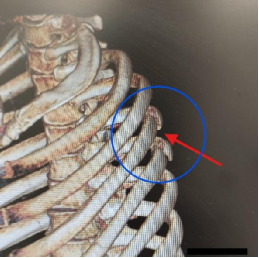

经过科室充分讨论后,决定为患者实施---胸腔镜下右侧第4、第5后肋骨折胸腔内反式环抱器内固定手术。

此手术方式的手术切口位于前胸壁,经胸腔内对断裂的肋骨进行复位、固定;手术切口较小,避免了肩胛骨周围更多的肌肉损伤,更避免了“掀开”肩胛骨可能导致肩胛骨骨折加重的风险。

术中胸腔镜下对断裂、错位的肋骨进行了复位及牢固的固定;术后复查肋骨CT见肋骨内固定位置合适、固定牢固(见图五);患者术后伤口恢复良好(见图六),已顺利出院。

图五 图六